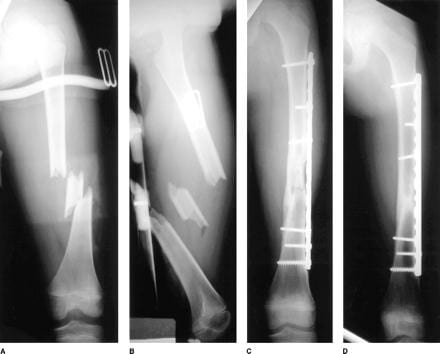

Perlukah membuang besi atau implan? û Dr Ahmad Mahyuddin | The Malaysian Medical Gazette

Perlukah membuang besi atau implan? û Dr Ahmad Mahyuddin | The Malaysian Medical Gazette

Untuk operasi patah tulang kaki

Untuk operasi patah tulang kaki

Lihat Hasil X-ray Bikin Ngilu! Begini Ternyata Patah Tulang Humerus Marc Marquez, Pelat dan 12 Baut Titanium Terpasang - GridOto.com

Lihat Hasil X-ray Bikin Ngilu! Begini Ternyata Patah Tulang Humerus Marc Marquez, Pelat dan 12 Baut Titanium Terpasang - GridOto.com

Plat Logam Pasca Fraktur : Perlu Diangkat Atau Tidak - Alomedika

Plat Logam Pasca Fraktur : Perlu Diangkat Atau Tidak - Alomedika